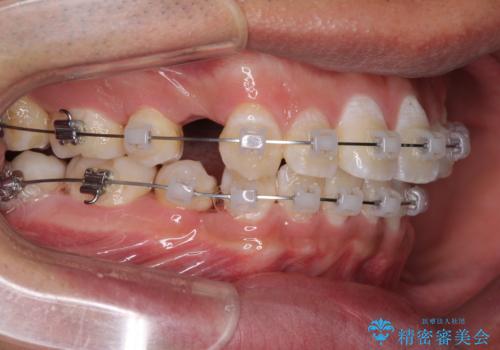

- クリアブラケット

- 3年3ヶ月

- 10-30回

奥歯の咬み合わせを改善したいため、治療期間が長くなりましたが、患者様には辛抱強くお付き合いいただきました。

上下の正中を合わせることもでき、患者様には大変満足していただきました。